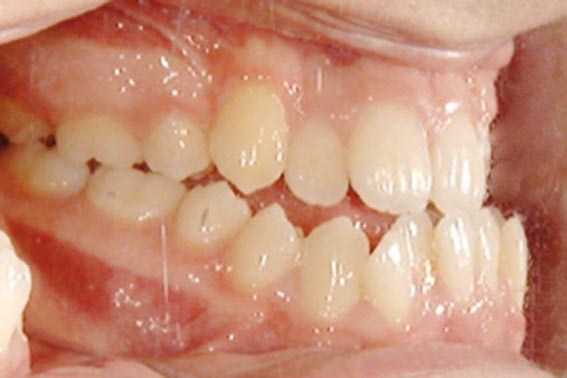

Les mouvements de décompensations sagittales et transversales sont réalisés à l’aide des tractions inter-arcades. La réévaluation céphalométrique et l’analyse des moulages confirment l’indication d’une chirurgie maxillaire de propulsion et d’une chirurgie mandibulaire par clivage bilatéral des branches montantes pour un recul mandibulaire modéré accompagné d’une génioplastie bidimensionnelle élargie qui rappelle la technique de Chin Wing.

Les résultats esthétiques et occlusaux satisfont amplement le patient qui revient pour un contrôle à long terme 10 ans après l’intervention montrant la stabilité des résultats.